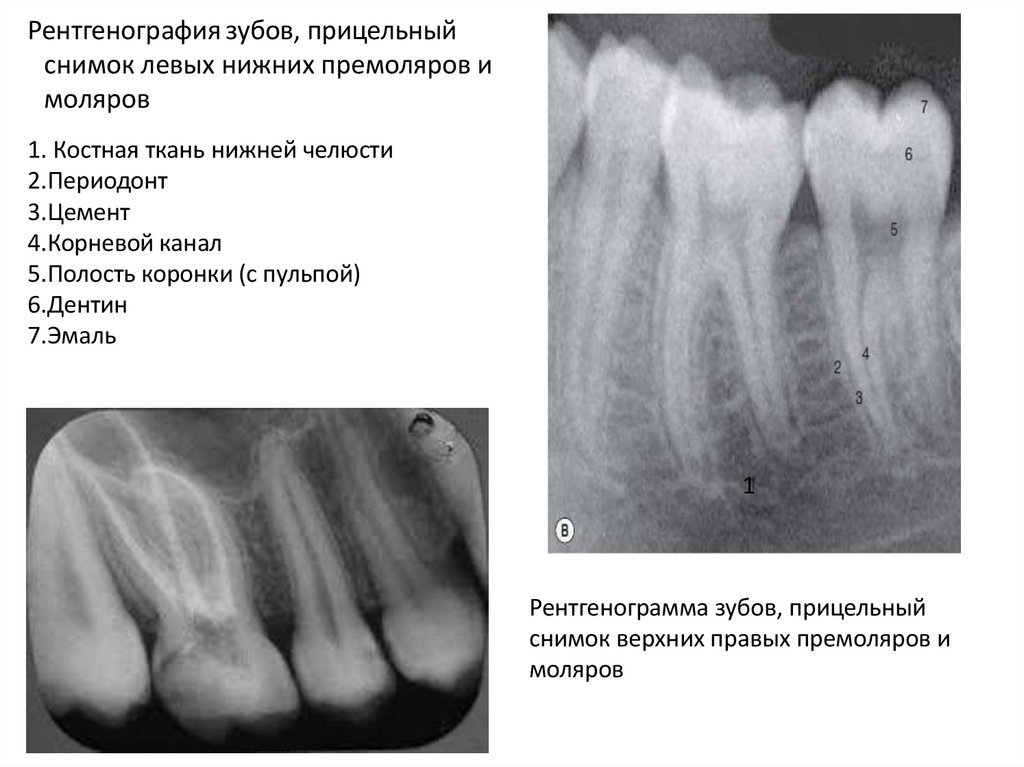

104.

Рентгенография зубов, прицельный

снимок левых нижних премоляров и

моляров

1. Костная ткань нижней челюсти

2.Периодонт

3.Цемент

4.Корневой канал

5.Полость коронки (с пульпой)

6.Дентин

7.Эмаль

Рентгенограмма зубов, прицельный

снимок верхних правых премоляров и